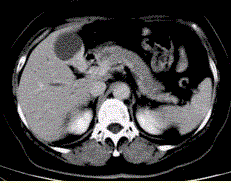

问题 患者女,50岁,右上腹痛,向肩胛部放射,伴有消瘦、乏力。查体:皮肤巩膜黄染,墨菲(Murphy)征阳性。CT示胆囊壁不规则增厚(下图)。 该病CT增强检查的表现为

选项 A.持续明显强化趋势 B.斑片状强化 C.呈“快进快出” D.延时期强化 E.未见明显强化

答案 A